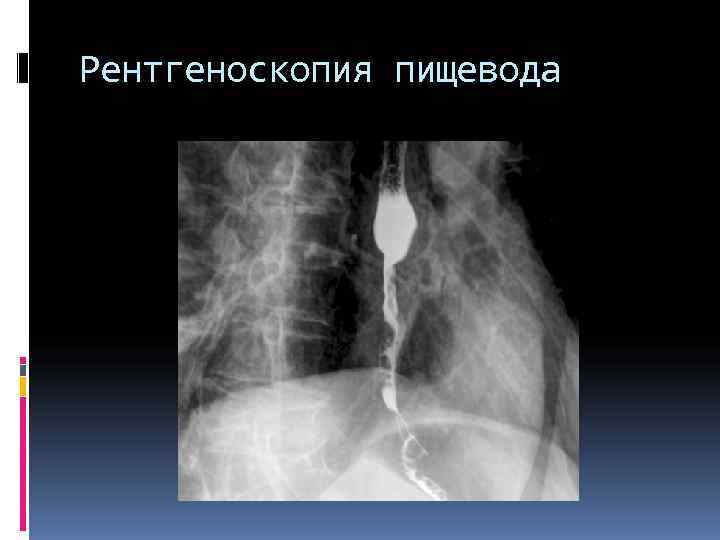

Рентгеноскопия пищевода

Физиологические сужения пищевода По ходу пищевода выявляются физиологические сужения: Первое из них находится у входа в пищевод, второе – на уровне дуги аорты, третье – на уровне бифуркации на уровне пищеводного отверстия диафрагмы. После прохождения основной части контрастной массы вырисовываются 2 -4 продольные параллельные другу складки слизистой оболочки, идущие на всем протяжении пищевода. Контуры тени контрастной массы в норме всегда ровные, слегка волнистые из-за перистальтических движений.

Контрастированный пищевод сдавление из-вне Аортальный сегмент